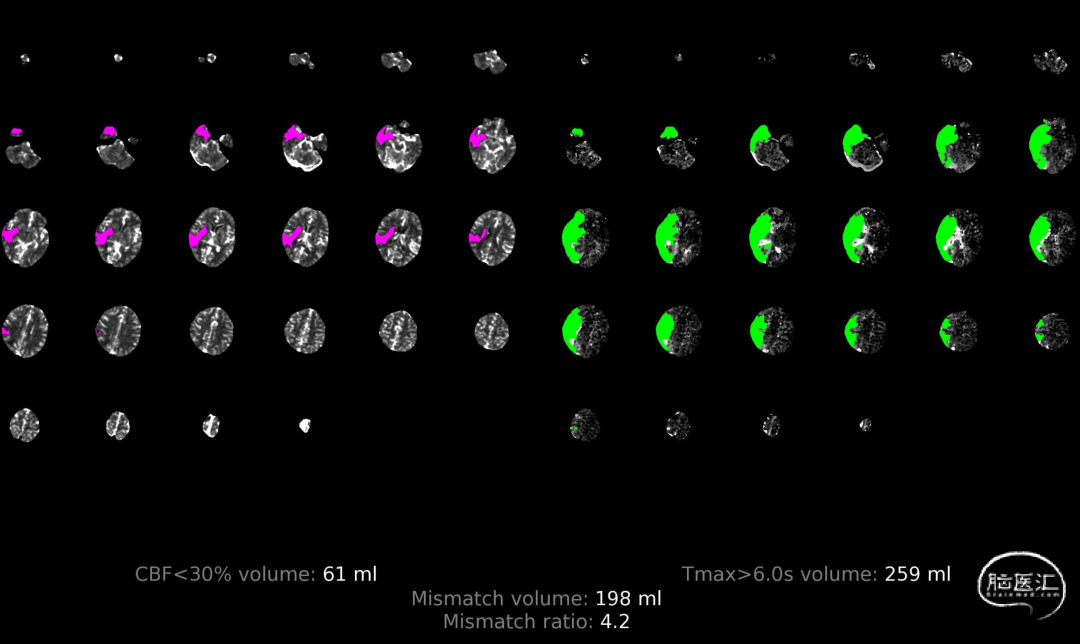

术前多模CT:右侧颈内动脉无嫌疑;CT平扫:大脑中动脉高密度帧,颞叶、岛叶脑沟、脑回灰质、白质分界不清;多模CT评估:缺血半暗带约198ml。